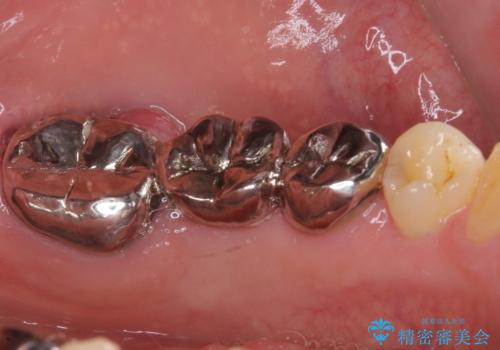

- 近医にてブリッジ治療を行った歯が痛くてたまらないとのことで来院された患者様です。

診察を行ったところ、奥の土台になっている歯は神経組織が失活しており、根尖部に病変があり、そこが原因で痛みを生じている状態でした。

根管治療を行うためにブリッジを除去したところ、むし歯が歯肉の奥深くにあまで及んでいたため、歯周外科処置によりむし歯が歯肉縁より浅い位置へと改善することとしました。